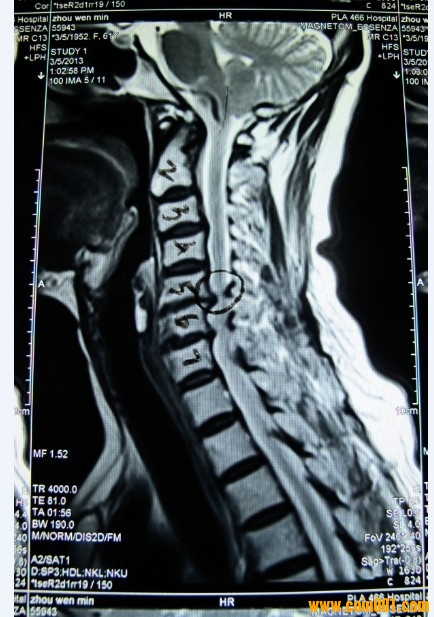

這是我丈母娘的頸椎核磁共振圖,5、6節(jié)頸椎椎管狹窄,問了幾家醫(yī)院都建議做手術(shù),

但是我丈母娘畢竟60多了,想盡量保守治療,有請網(wǎng)站懂這方面知識的會員給點(diǎn)建議,

建議是做手術(shù)好,還是不做手術(shù)好。哪個(gè)風(fēng)險(xiǎn)較小。60多歲的人了,哪種治療方式更

適合她。謝謝了。

脊髓型頸椎病!

報(bào)告上應(yīng)該寫著的吧?頸髓受壓明顯,

一般得這個(gè)的都是建議手術(shù)治療,我估計(jì)你丈母娘應(yīng)該有些癥狀的吧?比如走路不穩(wěn)像踩棉花等等。嚴(yán)重者走路經(jīng)常摔跟頭,尤其天冷的時(shí)候,有時(shí)候腿甚至?xí)ブX無法行走。

這個(gè)如果是年輕人的話,手術(shù)越早越好,否則頸髓繼續(xù)受壓有可能會癱瘓。

手術(shù)一般采用的是椎管減壓,椎體間融合,鈦板內(nèi)固定融合術(shù)。費(fèi)用一般在5,6萬元左右,如果有醫(yī)保,話花費(fèi)也就2萬,北京治療這個(gè)一般建議去北醫(yī)三院或者協(xié)和都行。

一般如果手術(shù)的話,住院時(shí)間大概在7-10天左右,然后會定期復(fù)查。手術(shù)時(shí)間一般在4,5個(gè)小時(shí)左右,

手術(shù)后導(dǎo)尿管導(dǎo)尿,第2天拔掉,佩戴頸托后由主管大夫扶起,陪床的開始幾天會比較辛苦,要有思想準(zhǔn)備。

現(xiàn)在的癥狀是一只手抬不起來,舉高就麻然后就抖。我丈母娘是會計(jì),估計(jì)是長期低頭所導(dǎo)致,現(xiàn)在醫(yī)院給的建議是盡量不讓低頭。